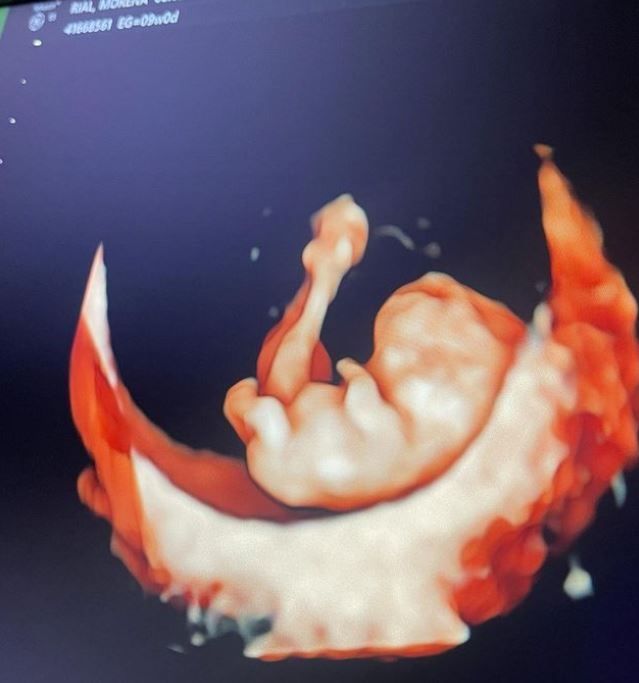

Por lo pronto, Bertorello cuenta con el gran soporte emocional que le brinda su novia, que continuamente le expresa su amor en redes, donde hace unos días mostró una imagen de la ecografía de su futuro hijo.

“Gracias por tu amor, por darme toda la seguridad y demostrarme día a día que todo lo que nos propongamos vamos a lograrlo. Te amo, sos todo en mi vida. Tenemos una hermosa familia y un hermoso bebe que viene en camino. Te amamos, papi lindo”, expresó More, quien transita su segundo embarazo.